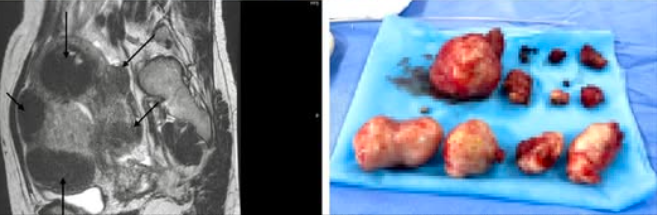

Các bác sĩ khoa Phụ Bệnh viện Sản Nhi Quảng Ninh vừa phẫu thuật thành công lấy 11 khối u xơ với nhiều hình dạng, kích thước phức tạp, tổng kích thước tương đương thai 5 tháng tuổi cho bệnh nhân nữ V.T.M (40 tuổi) thường trú tại Phường Móng Cái 3.

Kết quả siêu âm phát hiện bệnh nhân có nhiều khối u xơ nằm rải rác bao quanh tử cung, khối lớn nhất nằm ở thành trái L4 gần vòi tử cung, kích thước 79x68mm và L6 kích thước 68x39mm, khối u xơ ở đáy L5 có kích thước 51X48mm, có vôi hóa viền.

U xơ tử cung trên phim chụp và được lấy ra của bệnh nhân đa u xơ tử cung - Ảnh BVCC

Sau khi hội chẩn chuyên khoa, các bác sĩ chẩn đoán bệnh nhân bị đa u xơ tử cung phức tạp, chỉ định phẫu thuật gây mê nội khí quản để bóc tách u xơ. Quá trình bóc tách khối u, sau khi xử trí gỡ dính phức tạp mặt sau tử cung vào cùng đồ, mạc nối và buồng trứng trái, các bác sĩ đã tiến hành bóc thành công 11 khối u xơ, bảo tồn tử cung cho bệnh nhân, các mẫu bệnh phẩm được gửi giải phẫu bệnh, xét nghiệm, rất may các u đều lành tính.